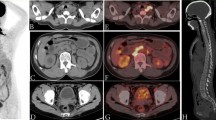

The growth of an allogeneic rapidly growing and metastasizing sarcoma (P-388) in the rat is described. Quantitative and kinetic data are provided concerning the growth of individual metastases produced in three principal regional lymph node drainage groups, and are compared with growth of the primary tumour of origin in muscle, the incidence of pulmonary metastases is also given. The effects on growth of metastases and primaries produced by sublethal whole body irradiation (WBI) before inoculations of 10-108 tumour cells are described.

Growth of P-388 sarcoma in unirradiated recipients (ED50 ≃ 5 × 103 cells) obeyed the linear growth law proposed by the Mayneord model for tumour growth, but in irradiated recipients (ED50 < 10 cells) early growth of primaries and metastases approximated more closely to an exponential rate of growth.

The ratio M/P of weight of metastases (M) to weight of primary tumour of origin (P) increased at a linear rate with age (t) of tumour, and gave the same slope namely, 0·029 for pelvic node metastases) in unirradiated rats inoculated with a large (106-107) number of cells as in irradiated rats. The slope was decreased to 0·014 for pelvic node metastases in unirradiated rats challenged with fewer (104) cells but not in irradiated recipients. It is postulated that the effects of WBI on growth of metastases are confined to causing a suppression of immunity, and that WBI does not affect tumour spread significantly through other mechanisms.